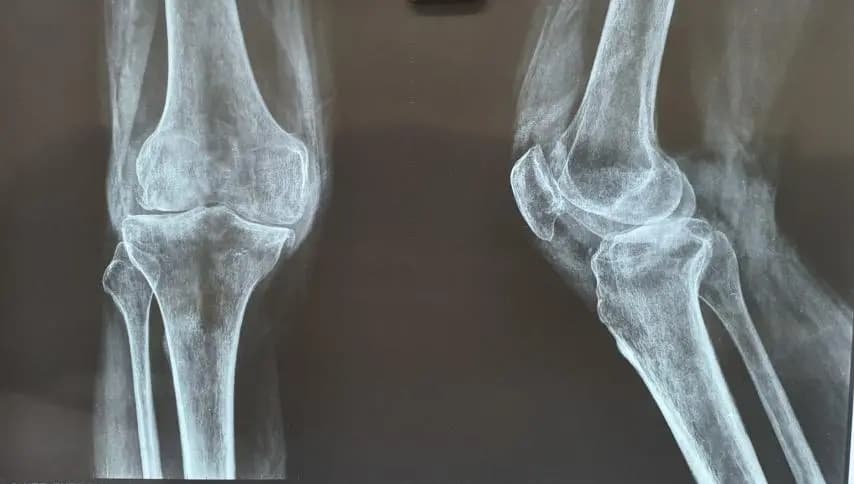

On-site digital X-ray, pre-surgical investigations, and imaging reviews in Sukhdev Vihar for faster, more accurate orthopedic decisions across South Delhi.

Digital X-rays for joints and spine with immediate image capture and viewing during your consultation.